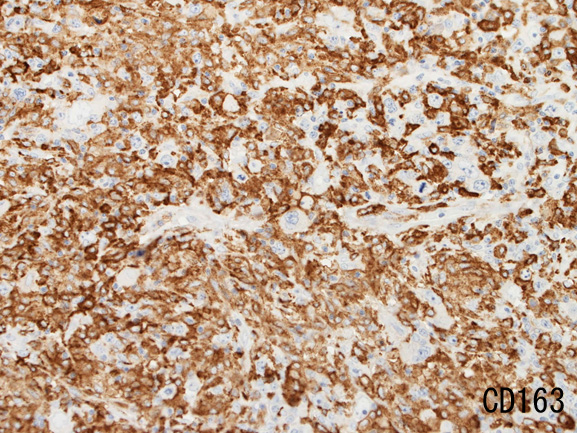

背景細胞はCD3+ Tリンパ球(CD8>CD4)とCD163, CD68陽性組織球。

背景組織球はCD163+